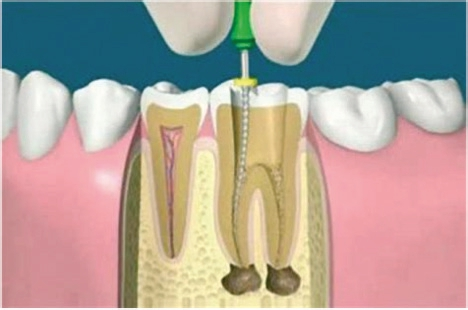

10) MIMI-Navigation: Beim MIMI-Verfahren bedienen wir uns einerseits der CNIP-Navigation (sagittale Navigation) und andererseits prothetischer Schablonen (mesial/distal orientierte Navigation), die für den Unter- und Oberkiefer immer wieder benutz-, sterilisier- und einsetzbar sind: Diese von Prof. Dr. A. El-Hamid (Casablanca) entwickelten Schablonen sind wirklich praktisch in der Handhabung: Man formt die Schablone extraoral entsprechend des Kieferkamms, legt sie am jeweiligen Kiefer an und erhält auf diese Weise die bestmögliche prothetische Position der zu inserierenden Implantate mit jeweils ausreichenden intraimplantären Abständen (Abb. 14). Die sagittal ausgerichtete CNIP-Navigation begleitet die Champions- Guides! Vergleichen kann man CNIP mit der Handaufbereitung von Wurzelkanälen bei einer Endodontie- Behandlung, bei der auch kein Kanal auf diese Weise perforiert werden kann. Analog des „weichen“ Nervkanals lassen die kompakten Außenwände (bukkal und oral) die konischen Dreikantbohrer nur in der „weichen“ Spongiosa des Knochens arbeiten, in die Tiefe gelangen und Kavitäten aufbereiten. Alle Bohrungen werden nur mit konischen Dreikantbohrern und 50–70 U/Min in der Spongiosa durchgeführt. Eine Perforation nach bukkal oder oral ist mit diesen Instrumenten bei diesen niedrigen Touren und deshalb auch mit Implantaten gänzlich ausgeschlossen! Dies gilt auch bei MIMI II-Behandlungen (Distraktion von schmalen Kieferkämmen ohne Mukoperiostlappen-Bildungen) (Abb. 15).